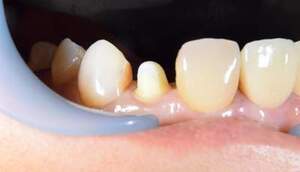

右上2が残根状態になっています。歯の保存をするためには歯を挺出させるしかありません。 |

左の写真は歯が歯肉縁上にないのがわかります。右では歯肉縁上に1周にわたって歯牙があるのがわかります。

レントゲンで見ても、右上2では歯質が歯肉縁上にのこっていない。しかし歯根は長いのでMTMの適応症例です。